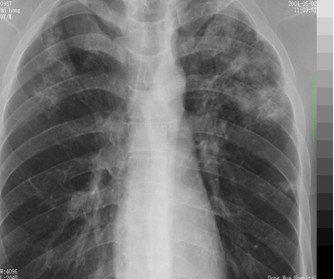

3. 胸部X线检查(下图):

早期:纹理模糊

实变:叶或段分布密度均匀的致密影

完全消散约3周左右

胸片示斑片状或整叶的浸润影

胸部X线检查